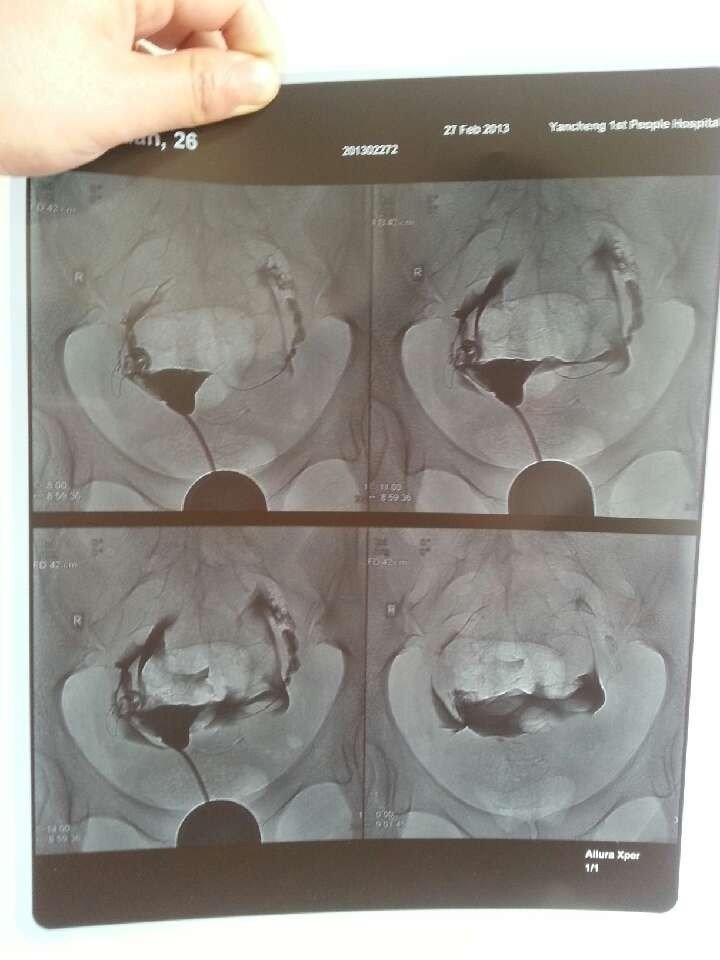

描述:造影剂导管注入宫腔略呈后倾位充盈良好。随后顺两侧宫角输卵管显影,呈线状纡曲走向自然。伞部较膨大,未见狭窄及梗塞征象。 随后观察,宫腔输卵管内造影剂已排空,见多量造影剂弥散于腹腔内,呈散在分布。 提示:子宫及输卵管造影未见器质性改变。